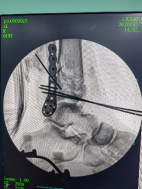

跟骨穿針并連接機器人

透視檢查骨折端